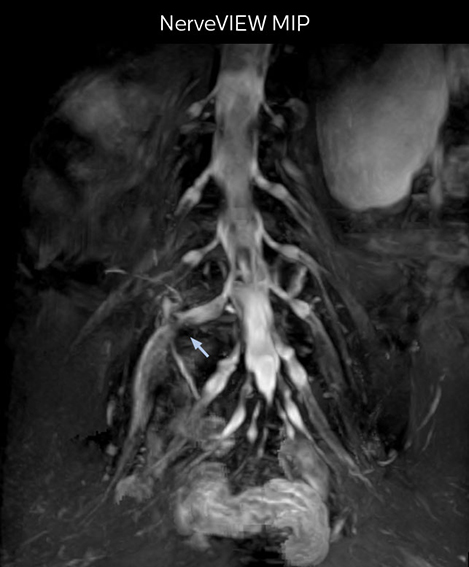

“In patients with lower extremity neurological symptoms, NerveVIEW helps us to determine the disease matching the patient’s symptoms by directly visualizing the nerves. We use the sequence mainly, when there is suspicion of intraforaminal stenosis, extraforaminal stenosis or lateral disc herniation, which is often based on routine T2- and T1-weighted images. Additionally, the excellent depiction of the course of nerves makes NerveVIEW a good navigator when applying treatment such as block therapy or surgery.”

“In such case, we would then browse through axial T2-weighted MR images slice by slice and mentally reconstruct the actual situation based on both radiculography and MRI. Fortunately, NerveVIEW can now very well show nerve courses and presence of nerve compression or edema in one single image series.” “We have often seen NerveVIEW directly depict details of the nerve compression that were not observed by radiculography. Therefore, we think that with NerveVIEW we can reduce the number of invasive examinations, especially for some patients with lumbar plexus symptoms.”

The key concept in MR neurography, Dr. Yabuki stresses, is the ability to directly visualize spinal nerves, versus inferring the presence of pathology indirectly. “Before NerveVIEW, we estimated compression of the nerve by looking for the presence or absence of fat signal on other MR images,” he says.

“For example, in sagittal images, when the presence of fat is observed in the intervertebral foramen, it suggests that there is a margin around the nerve. Similarly, the absence of fat indicates that the nerve is being compressed. So, we used to deduce nerve compression indirectly. With NerveVIEW, however, we can observe the condition of the nerves directly, regardless of the presence or absence of fat. We always prefer such direct observation of anatomy over having to make an inference about it.”

“Although symptoms of typical disc herniation and atypical hernia are very similar, the actual site of herniation is different. It is therefore important to characterize the nerve’s condition both inside and outside of the intervertebral foramina. “Conversely, if we see no abnormality in NerveVIEW, we can assume at least that there is no severe condition that requires surgery. Like this, it can help us avoid unnecessary surgery. NerveVIEW can have a tremendous impact in this way.”

“NerveVIEW is really useful for those cases where a nerve disorder is strongly suspected based on the clinical examination but our regular MRI images do not show any findings. These atypical herniations and spinal canal stenosis, occurring in 5% to 15% of the total lumbar herniation/stenosis cases are our main target when using NerveVIEW,” says Dr. Yabuki.

“The intra-luminal signal of veins, especially around the intervertebral space, can be suppressed well with NerveVIEW. As a result, we can easily observe the detailed nerve structure around the posterior ganglion,” he says. “This is why we use 3D NerveVIEW for intraforaminal stenosis and extraforaminal stenosis/herniation (lateral disc herniation). On the other hand, if herniation is suspected to exist inside the dorsal root ganglion (DRG), balanced TFE or ProSet-FFE is applied. NerveVIEW is not suitable for evaluating the median type of herniation.” The SE-EPI DWI-based method for MR neurography works well for large FOV exams like whole-body MRI, but focal examination of nerves is often limited by the attainable spatial resolution (both inplane and slice direction) and geometric distortion. “3D NerveVIEW achieves higher in-plane resolution – close to our other routine spine sequences – and the source images can be used instead of adding a fat-suppressed T2-weighted sequence,” Tanji says.